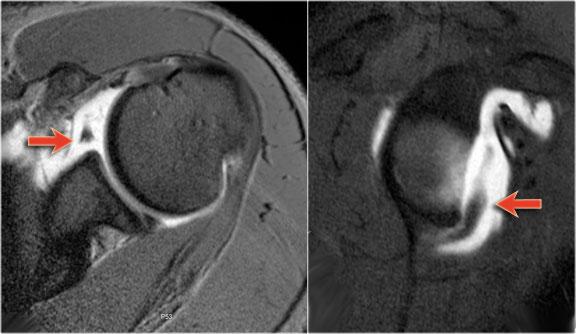

Tổn thương Bankart

Tổn thương Bankart là rách sụn viền không kèm mảnh xương.

Chụp MRI khớp cản từ hoặc nội soi khớp là phương pháp tối ưu để chẩn đoán tổn thương Bankart hoặc các tổn thương tương tự Bankart.

Có hình ảnh bong tách sụn viền trước-dưới (vị trí 3-6 giờ) với rách hoàn toàn màng xương bả vai phía trước.

Mũi tên chỉ vào màng xương bị gián đoạn.

Trên MRI khớp cản từ, sụn viền vắng mặt ở phía trước ổ chảo và mảnh sụn viền bị di lệch ra trước (mũi tên).

Tổn thương Perthes

Tổn thương Perthes là avulsion sụn viền-dây chằng tương tự Bankart, nhưng với màng xương bị bóc tách về phía trong mà vẫn còn nguyên vẹn.

Trên hình ảnh khớp vai ở tư thế trung gian, sụn viền bị rách có thể được giữ ở vị trí giải phẫu bình thường bởi màng xương bả vai còn nguyên vẹn, từ đó ngăn thuốc tương phản từ thấm vào đường rách.

Điều này có nghĩa là MRI khớp cản từ ở tư thế trung gian có thể không phát hiện được đường rách sụn viền.

Tuy nhiên, ở tư thế ABER, dây chằng ổ chảo-cánh tay dưới bó trước bị căng tạo lực kéo lên sụn viền trước-dưới, giúp tăng khả năng phát hiện đường rách.

Mũi tên chỉ vào màng xương còn nguyên vẹn.

Các hình ảnh ở tư thế ABER cho thấy sụn viền trước bị bong tách.

Hình bên phải được xoay 90° ngược chiều kim đồng hồ.

Đôi khi điều này giúp hiểu rõ hơn về giải phẫu.